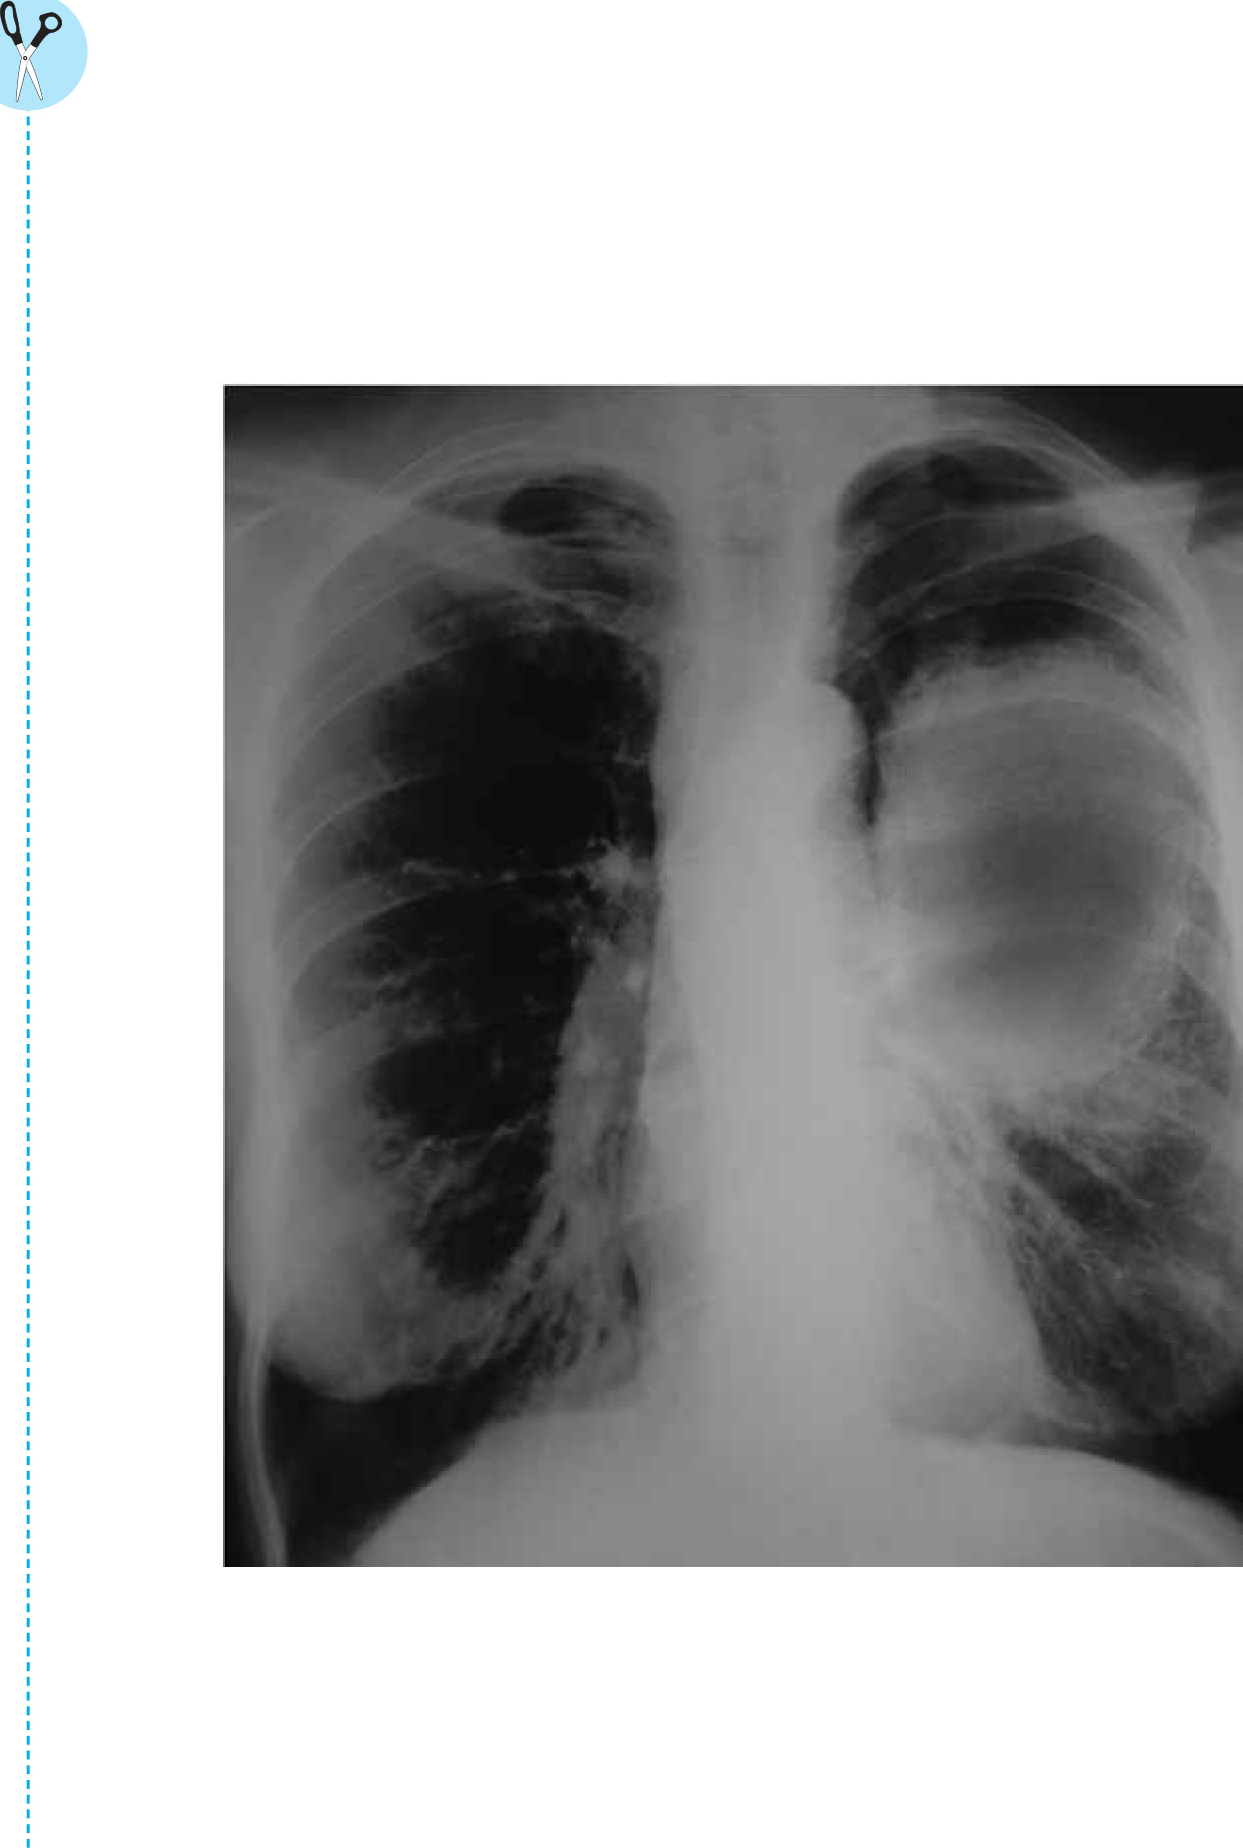

此外,香烟中含有一些有毒的化学物质,可能导致肺癌。医生使用X光检测病人是否患有肺癌。在X光片中,黑色的部分表示X光没有受到阻碍,白色的部分则表明X光遇到了一些障碍物,如致密组织或骨骼。

上一页是一张X光片,其中该病人左侧肺部患有癌症。此人60出头,这辈子吸烟成瘾,每天都抽很多支烟。他的肺部有大量的伤疤以及癌细胞,就是X光片上这些白色的组织。肺癌的后果是非常可怕的。比方说,癌细胞直径超过1英寸的患者,即使接受最有效的治疗,也只有不到一半的人能活过五年。像这个病人,根据他的X光片情况,也许他活不过一年。